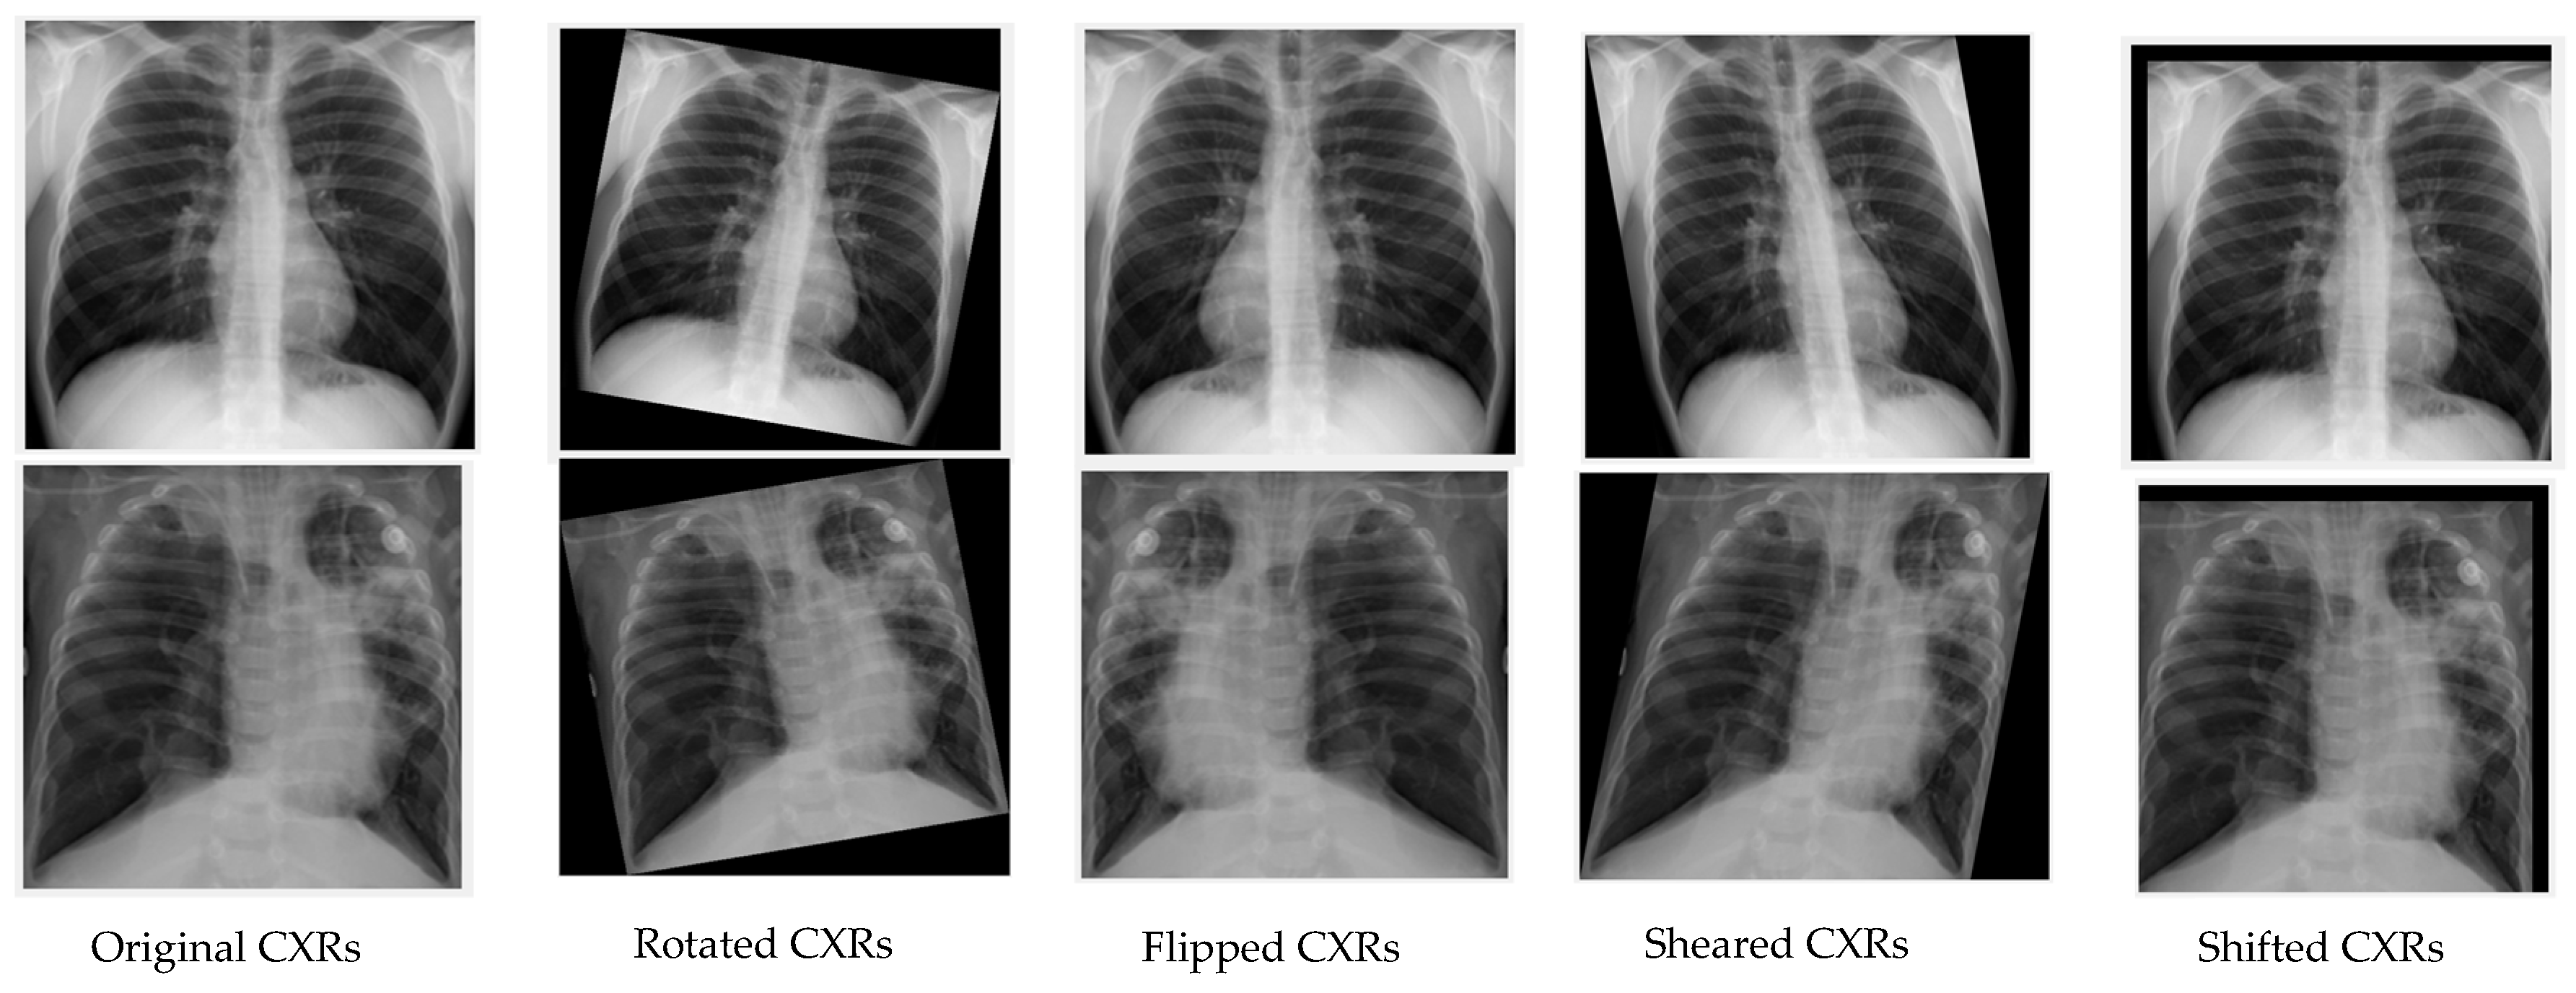

3.3.2. Approach 2: Deep Learning with Image Augmentation on an Unbalanced Dataset

- Nishio, M.; Noguchi, S.; Matsuo, H.; Murakami, T. Automatic classification between COVID-19 pneumonia, non-COVID-19 pneumonia, and the healthy on chest X-ray image: Combination of data augmentation methods. Sci. Rep. 2020, 10, 17532. [Google Scholar] [CrossRef]